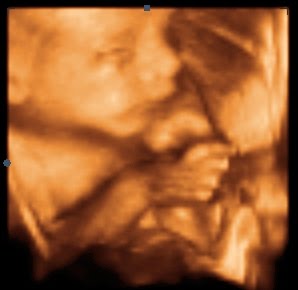

This is where I shed my first tear! He is sucking his thumb...it was so sweet, and he is so human like (of course) it is still shocking though to know that he is Alan and my son!